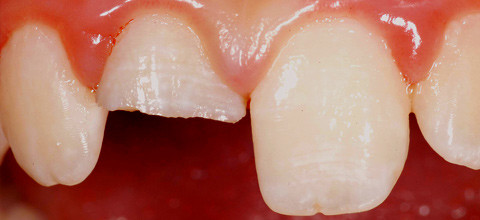

Für viele jugendliche Patienten ist der Grund für eine erstmalige invasive Therapie häufig die Behandlung traumatisierter Frontzähne. Oftmals ist das Wurzelwachstum der betroffenen Zähne noch nicht abgeschlossen. Abhängig von der Art der Verletzung und vom Zustand der Pulpa sind im Wesentlichen zwei Behandlungsoptionen für einen Zahnerhalt möglich.

Kam es zu einer Fraktur der Zahnkrone mit Beteiligung der Pulpa, ist von einer Infektion der Pulpa auszugehen. Es konnte jedoch nachgewiesen werden, dass auch nach mehrtägiger Exposition nur die koronalen 2–3 Millimeter bakteriell infiziert werden. Die Vitalerhaltung der Pulpa ist in diesem Fall anzustreben und die Behandlung erfolgt im Sinne einer Amputation des infizierten Gewebes. Unter Einhaltung steriler Kautelen werden die entzündeten Gewebeanteile mit einem schnell laufenden sterilen Diamanten unter Wasserkühlung entfernt. Die entstehende Blutung kann mithilfe steriler Spüllösungen (isotonische Kochsalzlösung) gestillt werden. Eine erfolgreiche Blutstillung spricht für eine vollständige Entfernung der entzündeten Gewebeanteile. Eine Nekrose der oberflächlichen Zellschichten durch die Blutstillung soll vermieden werden. Zur Überkappung der freiliegenden Gewebeanteile bietet Mineral Trioxide Aggregate (MTA) sehr gute Eigenschaften. Nach der vollständigen Aushärtung des Zementes ist eine unmittelbare, bakteriendichte definitive Versorgung des Zahnes ein wesentlicher Bestandteil für eine erfolgreiche Therapie.